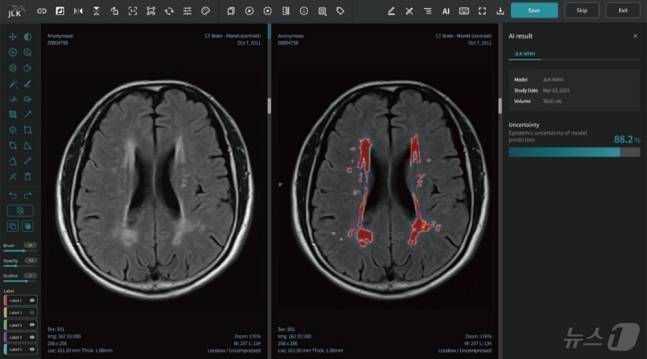

의료 인공지능(AI) 기업 제이엘케이는 자사가 개발한 대뇌백질변성분석 AI 솔루션(JLK-WMH)의 급성 뇌졸중 환자 대상 뇌백질변성 정량 분석 연구결과가 국제 학술지에 출판됐다고 22일 밝혔다.

제이엘케이 관계자는 "급성 뇌졸중 환자 8421명의 자기공명영상(MRI) 데이터를 AI가 학습하는 방식으로 개발돼 만성 뇌허혈병변에 해당하는 백질 변성 영역을 시각화하고 정략적으로 분석하는 솔루션 개발 과정과 성능 연구를 담은 논문"이라며 "국제 저명 학술지이자 미국 신경두경부영상의학회 학술지인 '아메리칸 저널 오브 뉴로라디올로지'에 최근 게재됐다"고 설명했다.

논문에 따르면 해당 솔루션은 급성 뇌졸중 환자의 MRI 영상을 분석해 환자의 백질변성 영역을 빠르고 정확하게 탐지하고 정량화한다. 10년 이상 경력을 보유한 전문의와의 정량 분석 일치도가 99%에 달하는 등 영상 데이터를 정량적으로 정확하게 분석했다는 평가다. 백질변성과 관련해 발생할 수 있는 치매를 비롯한 퇴행성질환의 조기 진단과 연구에 널리 활용될 것으로 기대를 모은다.

김동민 제이엘케이 대표는 “이번 JLK-WMH 논문 출판으로 제이엘케이 AI 솔루션의 우수성을 널리 알리게 됐다”며 “전 세계 1위 의료 시장인 미국 시장의 성공적 진출을 위해 회사의 모든 역량을 집중해 나갈 것”이라고 말했다.